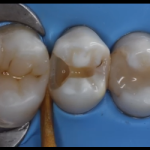

Una ricostruzione di seconda classe di Black in un secondo premolare